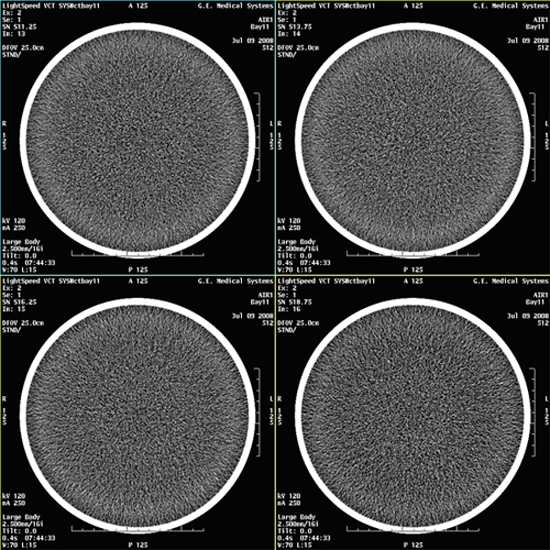

- Select VIEWER and review all images for

blotchy artifacts. (See Figure 1, Figure 2, and Figure 3). If an artifact is encountered, perform Tube Oil

Cooling System Air Removal.note:

If air artifact exists, the air activity may be more significant in Images 13 through 16, 29 through 32, 45 through 48, and 61 through 64.

Figure 1. Images with No Air Artifacts